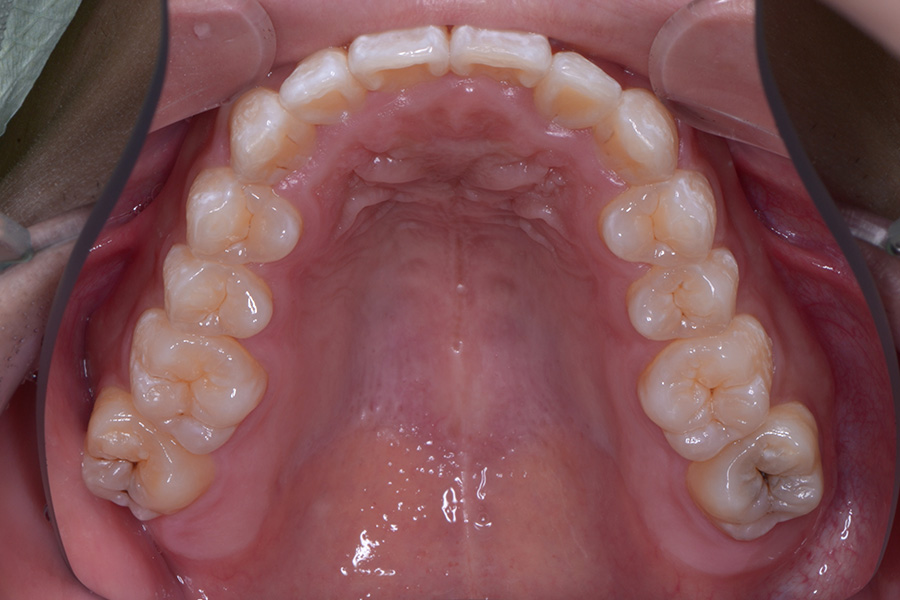

• 治療後

主訴 一本だけ隠れている歯を治したい

治療内容 上顎ラビアル矯正(表側矯正)